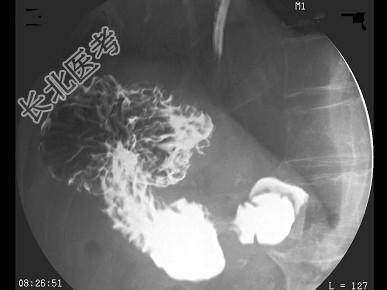

- 结合图像,最可能的诊断为 ( )